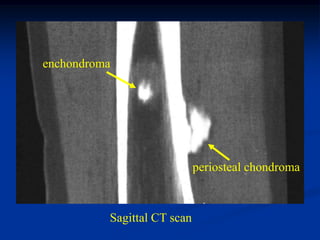

Case # 124.1                    AP and lat x-ray

50 year male with chondromyxoid fibroma proximal

tibia with 6 months of a tender tumor mass anterior tibia

Axial PD FS MRI